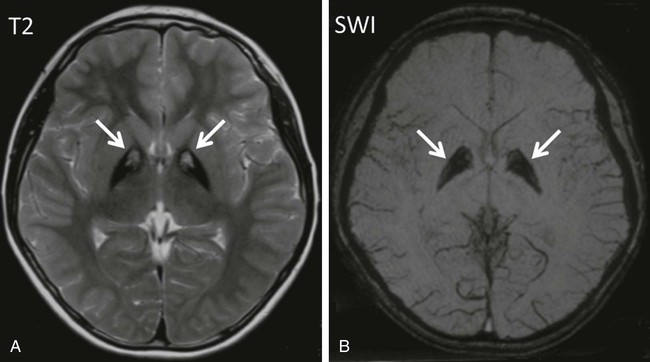

Pantothenate kinase–associated neurodegeneration (formerly known as Hallervorden-Spatz disease) is a rare autosomal recessive neurodegenerative disorder. Many patients have mutations in pantothenate kinase 2 (PANK2) localized to mitochondria in neurons. The condition usually begins before 6 yr of age and is characterized by rapidly progressive dystonia, rigidity, and choreoathetosis. Spasticity, extensor plantar responses, dysarthria, and intellectual deterioration become evident during adolescence, and death usually occurs by early adulthood. MRI shows lesions of the globus pallidus, including low signal intensity in T2-weighted images (corresponding to iron pigments) and an anteromedial area of high signal intensity (tissue necrosis and edema), or “eye-of-the-tiger” sign (Fig. 597-1). Neuropathologic examination indicates excessive accumulation of iron-containing pigments in the globus pallidus and substantia nigra. More recently, similar disorders of high brain iron content without PANK2 mutations, including infantile neuroaxonal dystrophy, neuroferritinopathy, and aceruloplasminemia, have been grouped as disorders of neurodegeneration with brain iron accumulation. Patterns of iron deposition visualized by brain MRI have shown utility in differentiating these disorders.